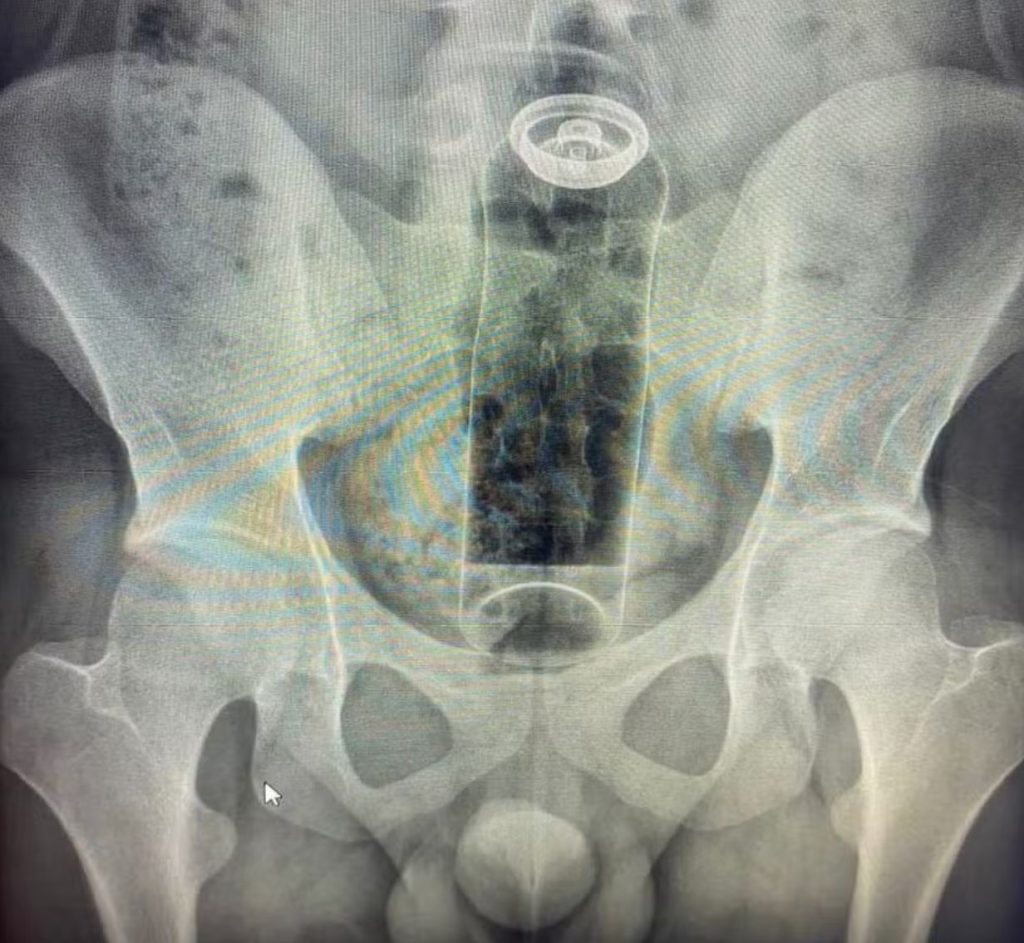

Seja por curiosidade, para apimentar a relação ou para experimentar a própria sexualidade, há quem goste de explorar o prazer na região anal na “hora h”. Especialistas explicam, no entanto, que é preciso cuidado com o que é introduzido. Um médico usou as redes sociais para fazer o alerta depois de atender um jovem que precisou ser internado para retirar um desodorante do reto. (Veja a imagem acima)

De acordo com o médico Daniel Brosco, cirurgião coloproctologista, o paciente tinha 19 anos e contou que colocou o desodorante no ânus durante uma “brincadeira” sexual. A embalagem, porém, acabou subindo para o reto e não conseguiu ser retirada em casa.